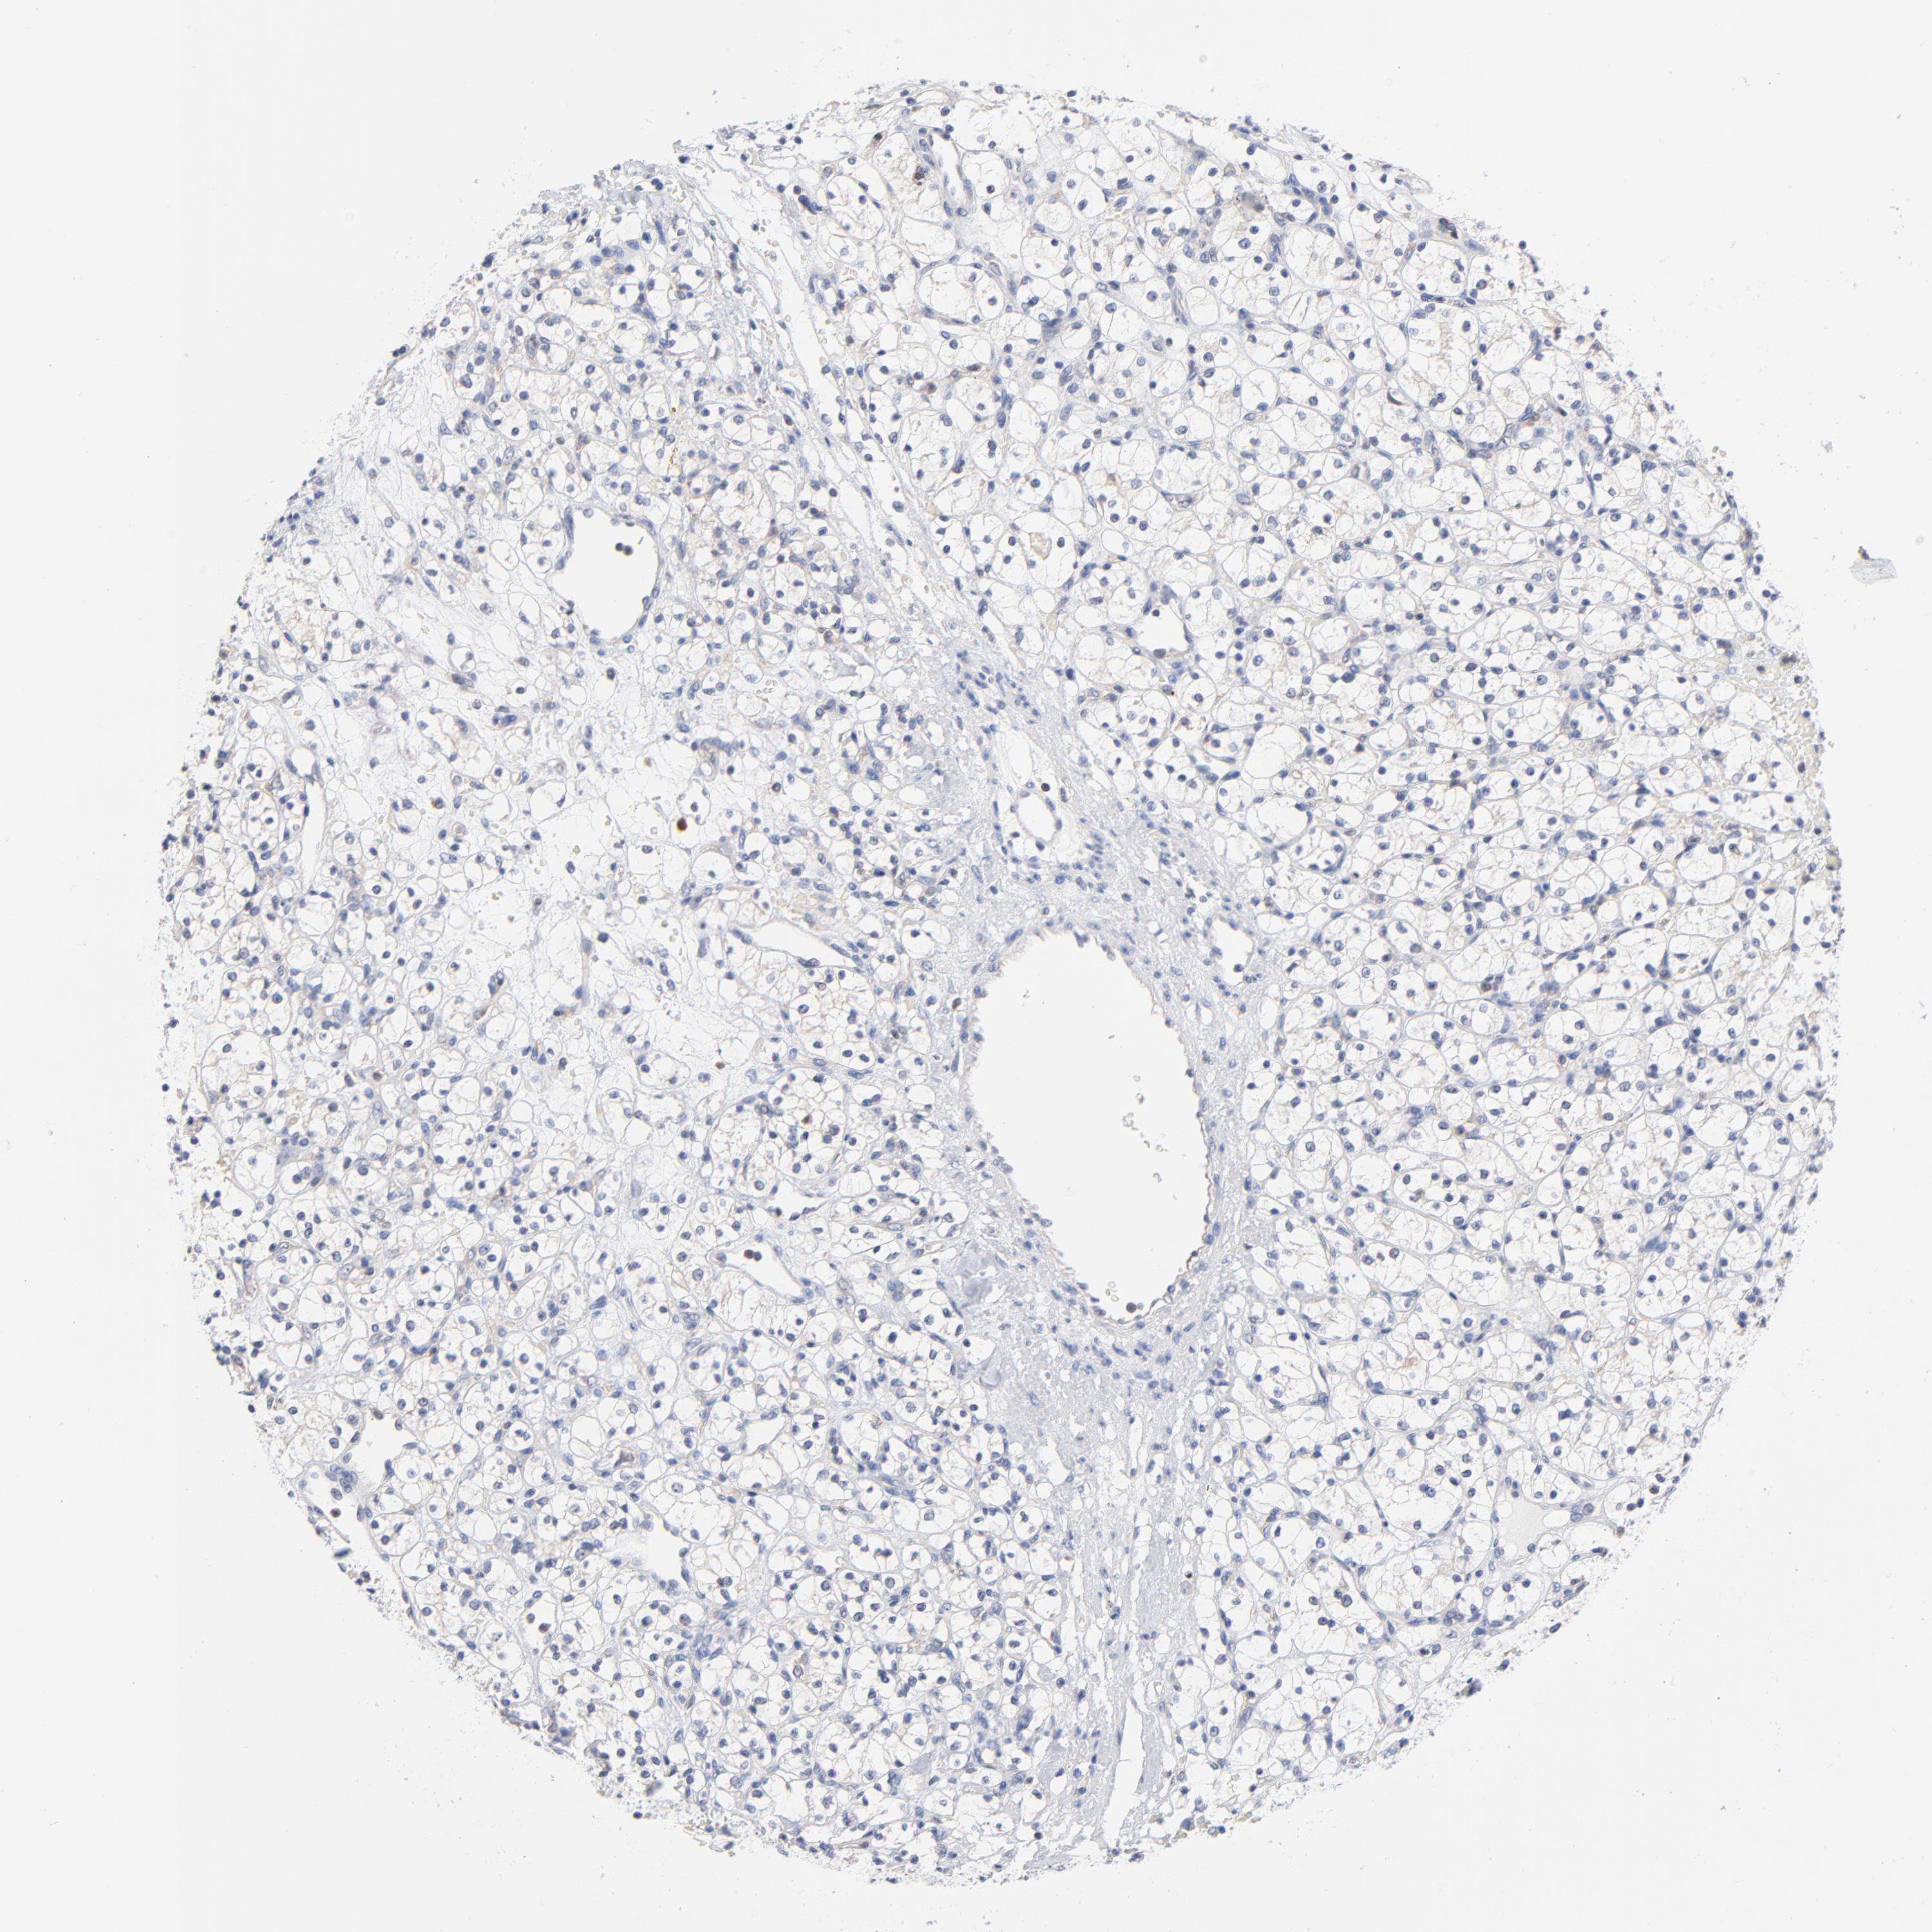

KIDNEY RENAL CLEAR CELL CARCINOMA (VALIDATION) - Interactive survival scatter ploti

The Survival Scatter plot shows the clinical status (i.e. dead or alive) for all individuals in the patient cohort, based on the same data that underlies the corresponding Kaplan-Meier plots. Patients that are alive at last time for follow-up are shown in blue and patients who have died during the study are shown in red.

The x-axis shows the expression levels (FPKM) of the investigated gene in the tumor tissue at the time of diagnosis. The y-axis shows the follow-up time after diagnosis (years). Both axes are complimented with kernel density curves demonstrating the data density over the axes. The top density plot shows the expression levels (FPKM) distribution among dead (red) and alive patients (blue). The right density plot shows the data density of the survived years of dead patients with high and low expression levels respectively, stratified using the cutoff indicated by the vertical dashed line through the Survival Scatter plot. This cutoff is automatically defined based on the FPKM cutoff that minimizes the p-score. The cutoff can be changed by dragging the vertical line or by entering a cutoff value in the square labeled "Current cut-off".

Under the Survival Scatter plot the p-score landscape (black curve; left axis) is shown together with dead median separation (red curve; right axis). Dead median separation is the difference in median mRNA expression between patients who have died with high and low expression, respectively. It is calculated as follows: median FPKM expression of dead patients with high expression - median FPKM expression of dead patients with low expression. This is intended to aid the user in visually exploring custom cutoffs and the associated p-scores and dead median separation.

Individual patient data is displayed and can be filtered by clicking on one or more of the category buttons on the top of the page. Categories describing expression level and patient information include: high, low, alive, dead, female, male and tumor stages. The scale of the x-axis can be toggled between linear and log-scale by clicking on the "x log" button. Mouse-over function shows TCGA ID, patient information and mRNA expression (FPKM) for each patient.

& Survival analysisi

Kaplan-Meier plots summarize results from analysis of correlation between mRNA expression level and patient survival. Patients were divided based on level of expression into one of the two groups "low" (under cut off) or "high" (over cut off). X-axis shows time for survival (years) and y-axis shows the probability of survival, where 1.0 corresponds to 100 percent.

CAB39L is not prognostic in Kidney Renal Clear Cell Carcinoma (validation)

Best expression cut offi

Based on the FPKM value of each gene, patients were classified into two groups and association between prognosis (survival) and gene expression (FPKM) was examined. The best expression cut-off refers the FPKM value that yields maximal difference with regard to survival between the two groups at the lowest log-rank P-value. Best expression cut-off was selected based on survival analysis .

When clicking on this number, the vertical dashed line indicating cut-off, the interactive survival plot, and the Kaplan-Meier curve will be adjusted to show results based on the best expression cut-off.

: 6.59

TCGA RNA samplesi

RNA-seq data is reported as average FPKM (number Fragments Per Kilobase of exon per Million reads), generated by the The Cancer Genome Atlas (TCGA) .

Normal distribution across the dataset is visualized with box plots, shown as median and 25th and 75th percentiles. Points are displayed as outliers if they are above or below 1.5 times the interquartile range. FPKM values of the individual samples are presented next to the box plot.

Average pTPM 6.8

Number of samples 100